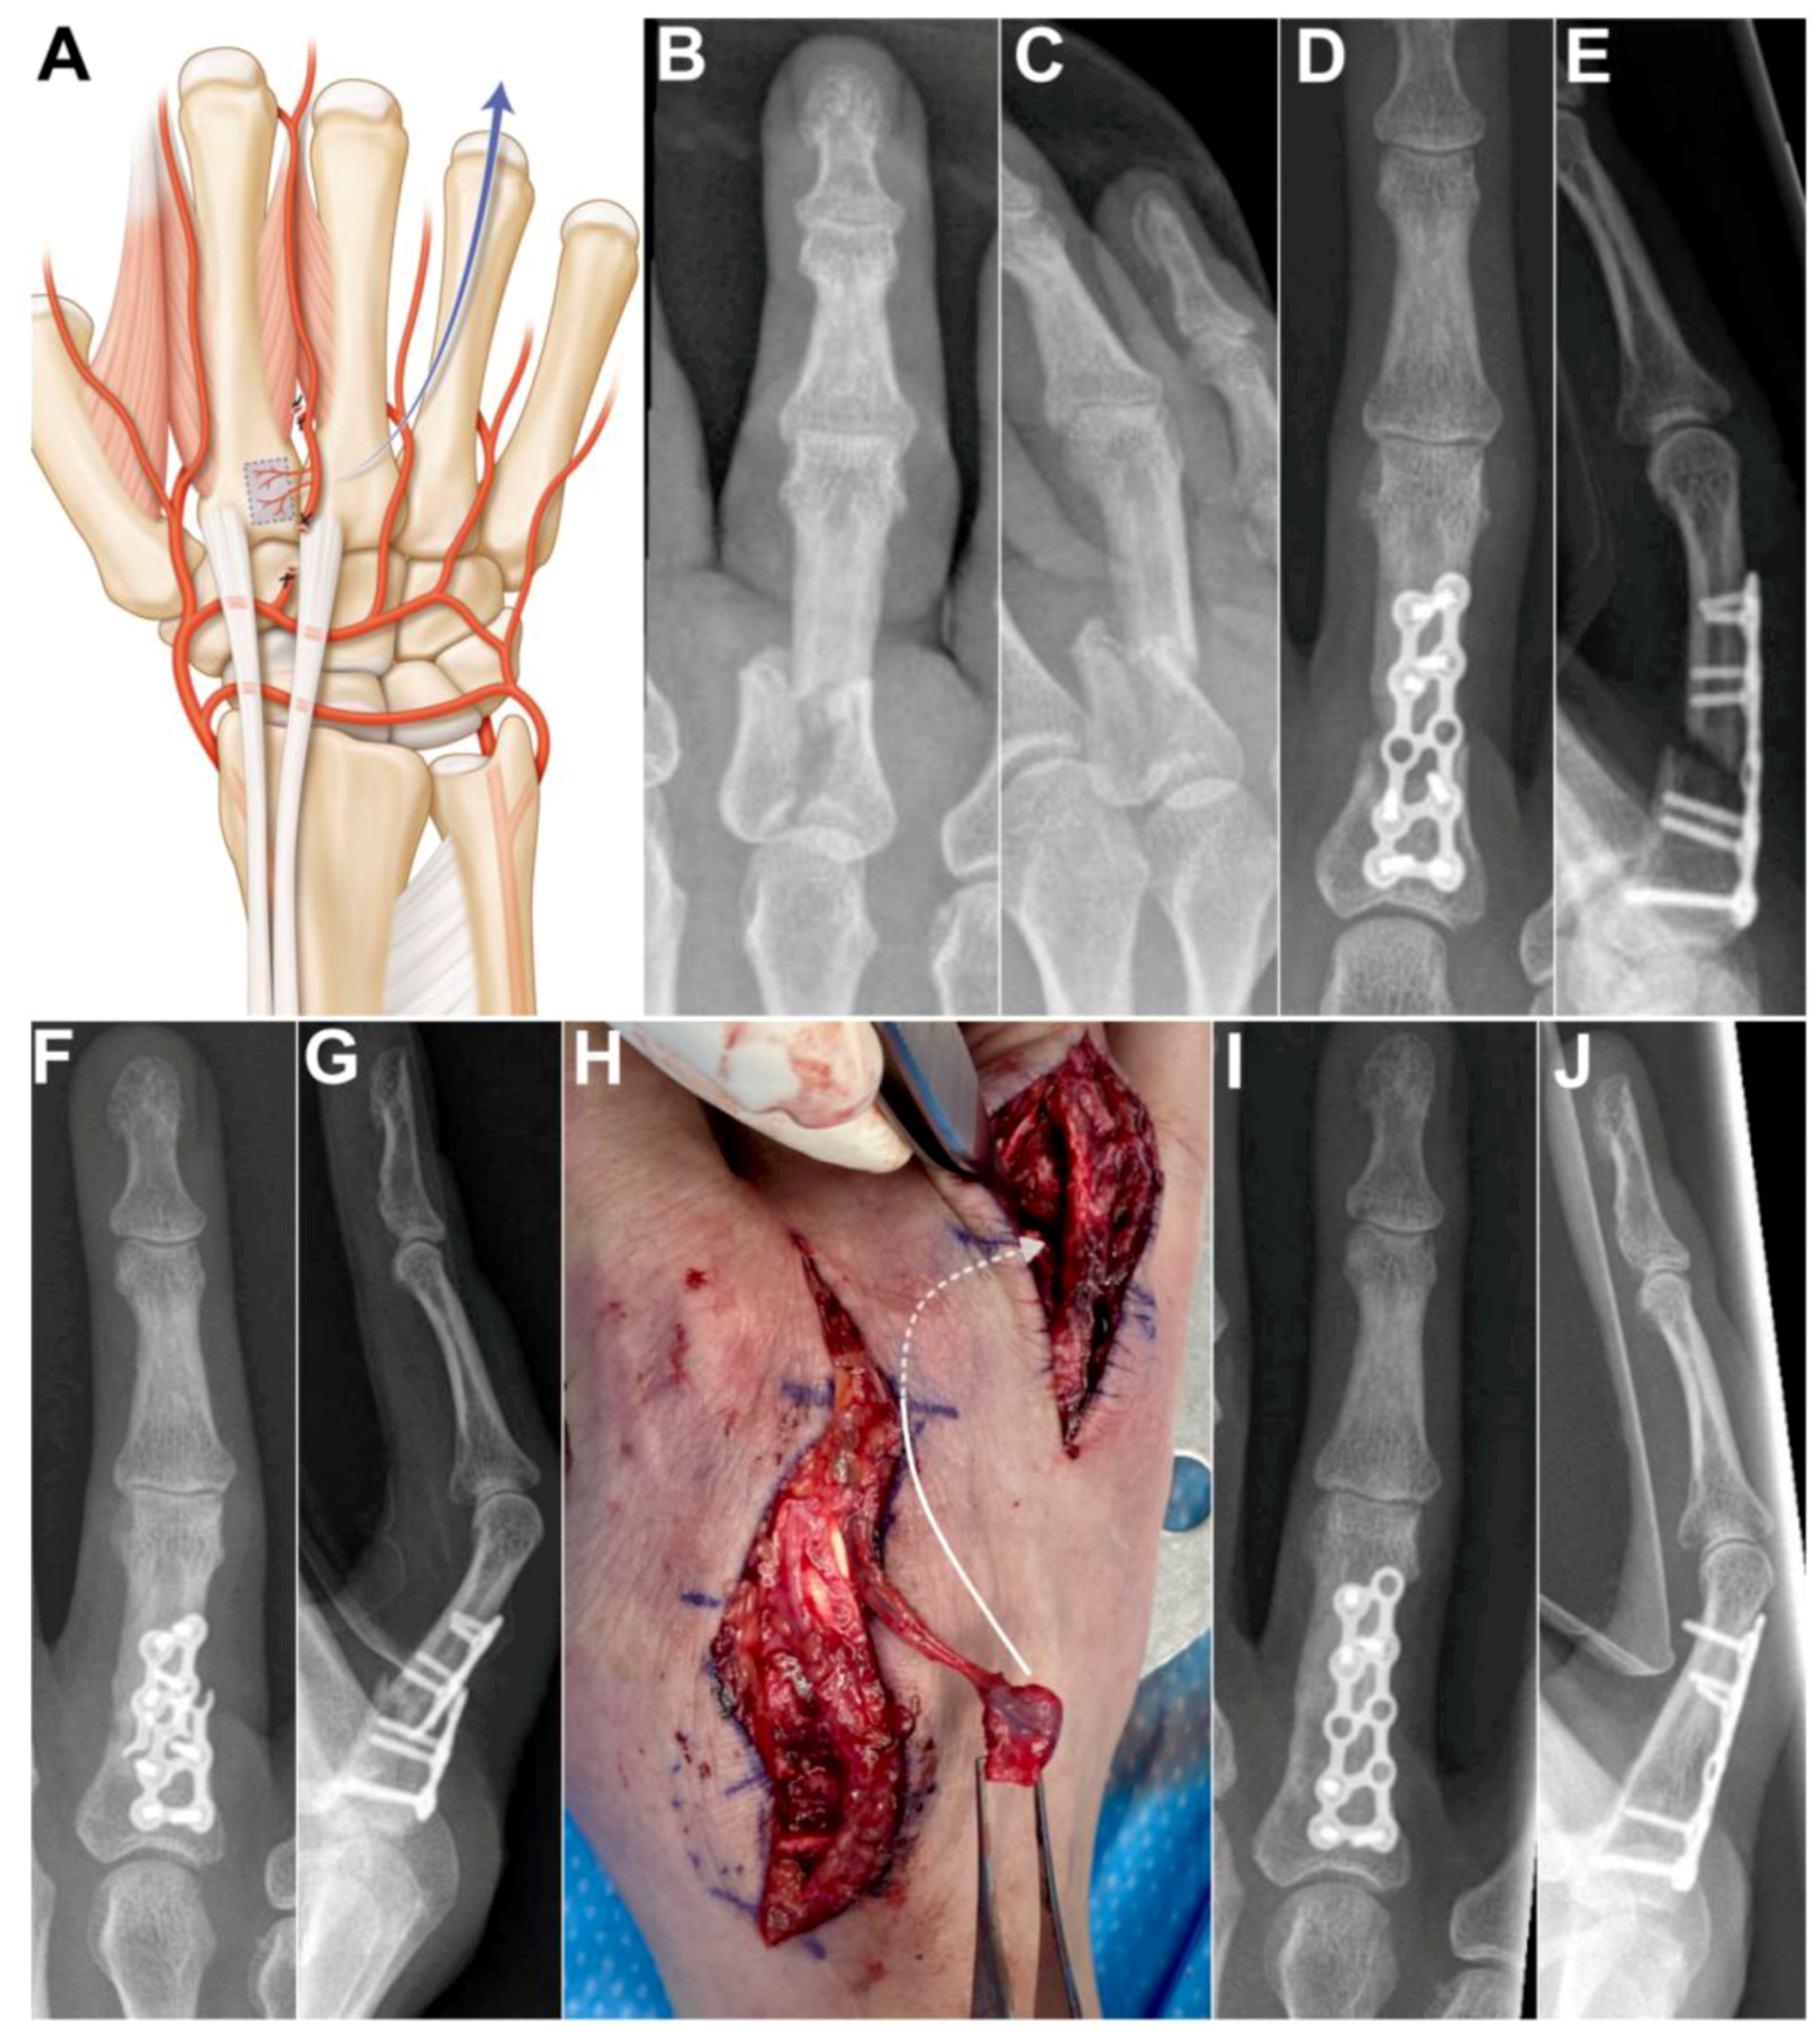

Case 4: A 53-year-old female presented with nonunion of the ring finger proximal phalanx seven months after an osteosynthesis with a dorsal plate and screws. The absence of bone healing led to hardware failure. A longitudinal incision was made over the 2nd metacarpal and another longitudinal incision over the first phalanx of the 4th ray. After bone debridement, a 1 cm gap remained between the bone stumps. The 2DMA was ligated proximally to the base of the second metacarpal. The proximal anastomosis with the deep palmar artery was ligated (Figure 5A). The 2DMA flap was pedicled distally on the distal penetrating branch of the deep palmar artery. Gentle dissection between extensor tendons and skin was made to allow passage of the vascularized 2nd metacarpal-base bone graft to the 4th ray. The size of the pedicled bone was 0.9 × 0.9 cm. A new plate and screws (Aptus, Medartis, Switzerland) provided stability. We witnessed bone union after ten weeks (Figure 5B–E). The patient was free of pain and recovered excellent grip strength (27 kg on the right hand and 30 kg on the left hand), and the range of motion (flexion/extension) was 75/25 degrees for the metacarpophalangeal joint, 55/−10 degrees for the proximal interphalangeal joint and 50/0 degrees for the distal interphalangeal joint of the finger. No complications were observed at the donor and recipient sites. Clinical and radiological outcomes were unchanged 2 years after surgery.

Figure 5. (A) Arterial anatomy, the distally based flap requires ligating the 2DMA proximally to the base of the second metacarpal as well as the palmar communicating branch; Case 4. (B,C) preoperative X-rays showing unstable and displaced intra-articular fracture of the first phalanx of the 4th ray. (D,E) postoperative X-rays, osteosynthesis with a dorsal plate and screws. (F,G) 7 months after osteosynthesis, X-rays showing unstable nonunion of the proximal phalanx after plate breakage; (H) Intraoperative photograph showing vascularized bone graft, dissection between extensor tendons and skin was made to allow passage of the vascularized 2nd metacarpal-base bone graft to the 4th ray (arrow). (I,J) postoperative X-rays demonstrating union of the phalanx.